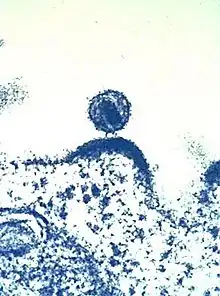

Hay muchos tipos de enfermedades crónicas, desde la diabetes y el VIH hasta la artritis y el cansancio persistente. Si bien, la ciencia médica ha logrado grandes progresos en el desarrollo de tratamientos eficaces para los efectos físicos de estas enfermedades, muchas víctimas siguen enfrentando un desafío asombroso para su salud mental y emocional.